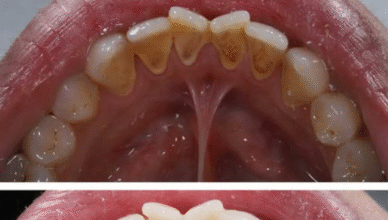

Czy zastanawiałeś się kiedyś, dlaczego mimo starannego mycia zębów, nie możesz utrzymać świeżego oddechu? Ten drobny problem, często pomijany, może szybko stać się